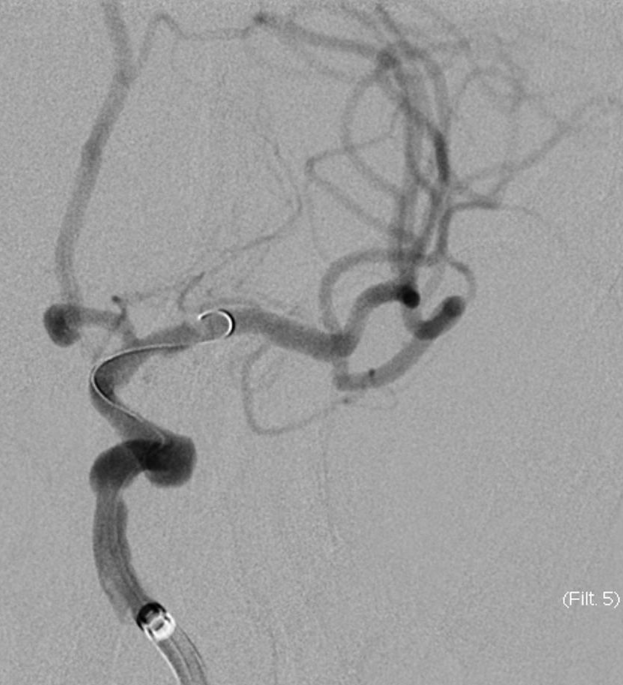

4mm×30mm Streamline

术后4月余随访:多发动脉瘤均未见显影,远端残余轻度狭窄

术前术后对比